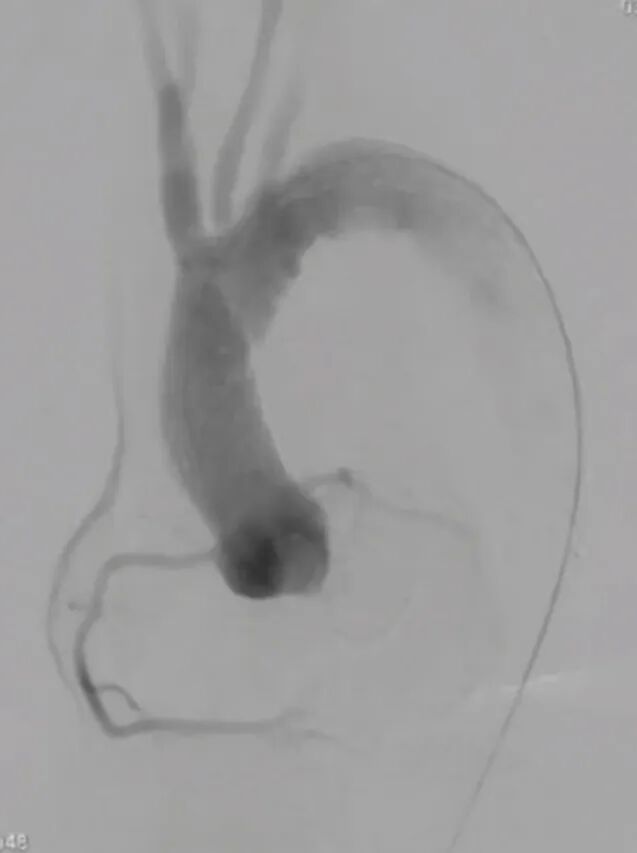

术后造影:主动脉夹层消失,无明显内漏,弓上三分支动脉显影通畅。降主动脉真腔增大,显影通畅,内脏动脉显影良好。颅内动脉显影通畅,未见明显栓塞影像。

波科支架怎么样陆信武:激光原位开窗重建弓上分支治疗A型主动脉夹层_https://www.jmylbn.com_新闻资讯_第9张波科支架怎么样陆信武:激光原位开窗重建弓上分支治疗A型主动脉夹层_https://www.jmylbn.com_新闻资讯_第10张波科支架怎么样陆信武:激光原位开窗重建弓上分支治疗A型主动脉夹层_https://www.jmylbn.com_新闻资讯_第11张

支架植入后:术后12个月随访:复查主动脉CTA可见主动脉重塑良好,弓上三分支显影通畅,无内漏形成。